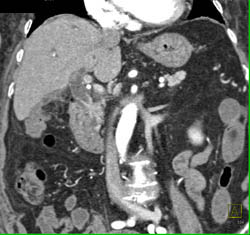

Cholangiocarcinoma of the Distal Common Bile Duct (CBD) Which Is Enhancing- See Full Sequence